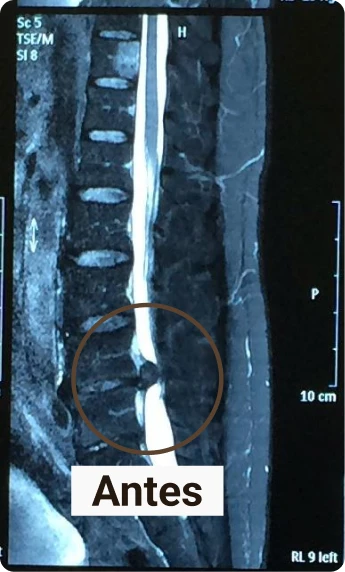

Veja por exemplo esse caso, paciente estava com uma hérnia de disco grande, ficou preocupado quando recebeu o diagnóstico do exame, já era indicação cirúrgica, mas em poucas sessões conseguimos reverter, somente com o tratamento conservador.

O tratamento foi sem necessidade de cirurgia